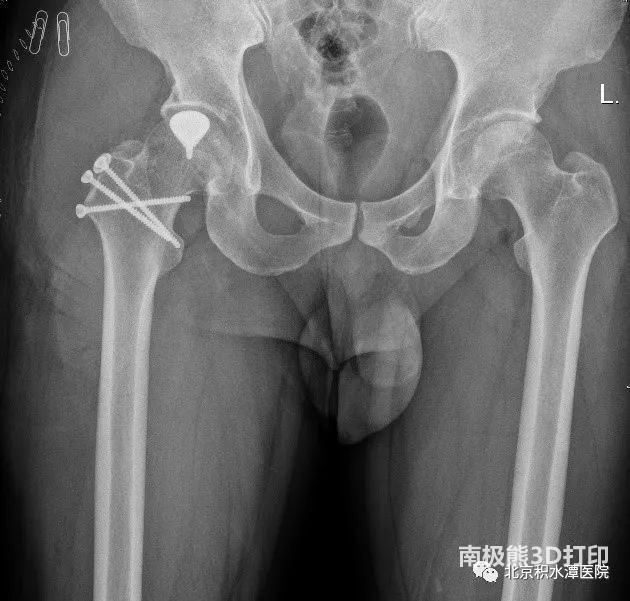

本次进行手术的两名患者均为年轻男性,其中小昭(化名)仅20岁左右,还是父母的心头肉。门诊通过髋关节X光,CT及MRI检查发现,小昭髋关节股骨头坏死,坏死区已经塌陷,但关节间隙正常,尚无明显骨关节炎表现。同时患者年轻,要求尽可能保留健康骨质。周一新教授团队通过对病情的综合判断,除了提供全髋置换等传统治疗选择之外,给了患者另一个选择——定制部分髋关节置换术。在充分沟通各种治疗选择的优劣后,小昭及家属决定选择定制部分髋关节置换术这一创新术式。

▲患者术前影像学资料显示右股骨头坏死,坏死区部分塌陷,但关节间隙正常,尚无明显骨关节炎。